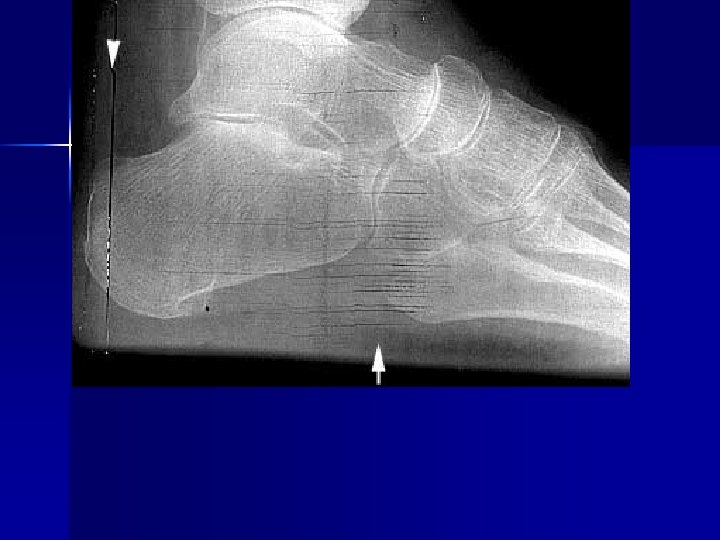

Name & cause of this?

Evaluating Images What do you think?

n n n Does this show good detail? Is all of the anatomy present? How is the density / contrast?